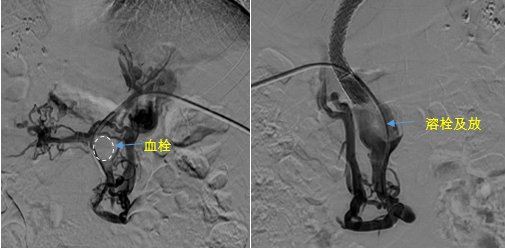

在西安國(guó)際醫(yī)學(xué)中心醫(yī)院,韓國(guó)宏教授對(duì)李女士進(jìn)行了細(xì)致的問(wèn)診及檢查,在CT圖像上仔細(xì)的分析,針對(duì)患者特殊的病情制定了詳細(xì)的治療方案。第一次進(jìn)入手術(shù)室,在DSA的監(jiān)測(cè)下,造影過(guò)程中門靜脈血栓的輪廓逐漸顯現(xiàn)出來(lái),見(jiàn)多識(shí)廣的醫(yī)生們也大吃一驚,發(fā)現(xiàn)遠(yuǎn)端脾靜脈及腸系膜上靜脈也存在大量血栓。患者的食管胃底靜脈曲張非常嚴(yán)重,疏通堵塞的門靜脈已是刻不容緩。

見(jiàn)此情形,韓國(guó)宏教授憑借豐富的臨床經(jīng)驗(yàn)很快調(diào)整了策略,在超聲診療中心的協(xié)助下進(jìn)行門靜脈右支穿刺,并進(jìn)行造影,看到目標(biāo)血管后,韓國(guó)宏教授用“明修棧道,暗渡陳倉(cāng)”的方法,讓來(lái)自脾臟和胃腸的血流終于暢通的回流到了肝靜脈。通過(guò)血流的沖刷以及抗凝溶栓藥物的作用,幾日后復(fù)查造影發(fā)現(xiàn)門靜脈血栓已逐漸變小,不會(huì)對(duì)回流到肝臟的血流產(chǎn)生大的阻礙作用,門靜脈的壓力顯著減小,患者再次出血的幾率也隨之降低。幾經(jīng)周折,這顆“定時(shí)炸彈”終于被拆除,李女士和她的家人多年來(lái)心里的石頭也終于落地。